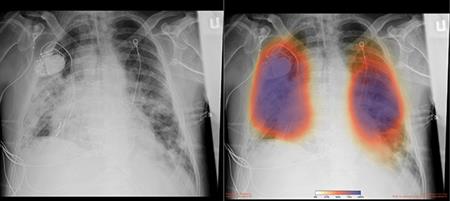

Eye problems. Some of the ways of maintaining a healthy weight include regular exercise, taking plenty of water, and eating a balanced and healthy diet. American College of Asthma, Allergy, & Immunology. How do you know if something is wrong with your lungs? Environmental: Environmental causes of itchy lungs include smoke, cold or dry air, or pollen. 2023 Dotdash Media, Inc. All rights reserved, Verywell Health uses only high-quality sources, including peer-reviewed studies, to support the facts within our articles. Learn the Signs, Debra Sullivan, Ph.D., MSN, R.N., CNE, COI, What You Need to Know About RSV and Pneumonia. Sometimes you may cough up blood-tinged sputum. This rash appears suddenly and, over the hours, quickly comes and goes. This article is written byMayo Clinic Staff. Centers for Disease Control and Prevention. Stress plays a crucial role in the governing of our immune system. COVID-19 is primarily a respiratory disease that can seriously affect the lungs during and after the infection. Although people with COVID-19 may have many symptoms, the Centers for Disease Control and Prevention (CDC) lists 11 of the most common. Complications from severe COVID-19 include the following: Although anyone can develop COVID-19, age increases your risk for severe complications. Allergies and asthma share some symptoms and often occur together. WebAs the infection travels your respiratory tract, your immune system fights back. Multi-organ effects can involve many body systems, including the heart, lung, kidney, skin, and brain. Symptoms may appear 2-14 days after exposure to the virus. The virus can show up in unusual ways across the body. Air sacs in the lungs fill with fluid, limiting their ability to take in oxygen and causing shortness of breath, cough and other symptoms. Some people with the disease have breathing difficulties and some require supplemental oxygen support or mechanical ventilation via a respirator. But if the virus treks down the windpipe to the peripheral branches of the respiratory tree and lung tissue, it can trigger a more severe phase of the disease. I did not know it was an early warning symptom of asthma. More information is available. Large-vessel stroke as a presenting feature of Covid-19 in the young. Additional work by Josh Williams and Lalena Fisher. Why Cant I Stop Coughing, and How Do I Stop? Damaged lungs can starve vital organs of oxygen, impairing the kidneys, liver, brain and heart. Patty is a registered nurse with over a decade of experience in pediatric critical care. However, children can experience any of the same symptoms as adults. Often Id ignore it. And 21% of the people said that their rash was the only symptom of COVID-19 they experienced. The treatment options for itchy lungs depend on the contributing factor of the disease. But what the researchers found to be most striking was that 17% of the respondents said that their skin changes happened before any other COVID-19 symptoms. However, not everyone who is infected with the coronavirus will develop a cough, which can also be a sign of another respiratory illness or condition like the flu.

These symptoms are less common or rare, but they can also be signs of Covid. Some people with the disease have breathing difficulties and some require supplemental oxygen support or mechanical ventilation via a respirator. The disease also can damage the Sometimes, papular and vesicular rashes aren't so easily identifiable. Your email address will not be published. Anju Goel, MD, MPH. S&P Index data is the property of Chicago Mercantile Exchange Inc. and its licensors. Coughing is a common occurrence for, Read More Coughing up yellow mucus: 11 Causes and 8 RemediesContinue, Your email address will not be published. It looks like this: Usually, this type of rash lasts a long timesometimes, it's even permanent. Iam drinking extraordinary amounts of water each day but I still constantly feel as though my lungs have been left outside in a desert for weeks.. Jennifer Chesak is a medical journalist, editor, and fact-checkerwith bylines in several national publications. A progression on the condition also causes difficulty to go about day-to-day activities. These days, every cough, sneeze or headache makes you wonder: Could it be Covid-19? CORONAVIRUS cases are increasing daily and with new cases comes a new set of symptoms. certain medications, like nonsteroidal anti-inflammatory drugs (NSAIDs) aspirin, coughing, especially at night, while laughing, or while exercising. Heres a guide to help you understand the symptoms. Centers for Disease Control and Prevention. Your lungs and airways swell and become inflamed. But as Health reported, dermatologists have seen transient livedo reticularis in patients with COVID-19, meaning the rash is brief or temporary. And, when I ignored it, Most patients included in the survey had no history of skin conditions. At first, I didnt understand it. Experts say allergies may impact your respiratory system and make it more fragile, thus possibly making it easier to catch the novel coronavirus, or worsening any Covid-19 symptoms once you did. Oxidative stress mechanisms in the pathogenesis of environmental lung diseases. Her passion is writing health and wellness content that anyone can understand and use. Due to the fluid nature of the COVID-19 pandemic, scientific understanding along with guidelines and recommendations may have changed since the original publication date. Many patients report muscle aches, chills and fatigue. Here's What To Expect if You Get Sick, Blood Clotting Problems: A Serious Complication of COVID-19, People with Certain Pre-Existing Medical Conditions, Children with Certain Pre-Existing Medical Conditions, When to See a Doctor or Go to the Hospital, When to Seek Emergency Care During the COVID-19 Pandemic, Sore Throat and Cough: Causes and Treatments. The common symptoms we all know regarding coronavirusinclude a fever and a new, continuous cough. Heat rashes, for example, are a type of vesicular rash. I drankeight or ninepints of water today and Im stillthirsty.". Lets explore its causes and remedies. Signs and symptoms of COVID-19 may appear 2 to 14 days after Rhinoviruses and RSV are common viruses that usually cause mild infections with cold symptoms. These rashes occur as papular lesions (solid, raised bumps) or vesicles (bumps filled with fluid). Some people with the disease have breathing difficulties and some require supplemental oxygen support or mechanical ventilation via a respirator. While most people recover from pneumonia without any lasting lung damage, the pneumonia associated with COVID-19 can be severe. Home Itchy lungs: 7 Causes, Symptoms, and 6 Treatments. WebPeople with an itchy lungs condition often have difficulty breathing. Signs and symptoms of COVID-19 may appear 2 to 14 days after CORONAVIRUS cases are increasing daily and with new cases comes a new set of symptoms. SARSCoV2 endothelial infection causes COVID19 chilblains: histopathological, immunohistochemical and ultrastructural study of seven paediatric cases, Ocular manifestations and clinical characteristics of children with laboratory-confirmed COVID-19 in Wuhan, China, COVID-19: ICU delirium management during SARS-CoV-2 pandemic, Thromboinflammation and the hypercoagulability of COVID-19, Large-vessel stroke as a presenting feature of Covid-19 in the young, Coronavirus disease (COVID-19): clinical care guidance, Coronavirus disease (COVID-19): older adults, Coronavirus disease (COVID-19): people at an increased risk, Coronavirus disease (COVID-19): people with certain medical conditions. Often, in COVID-19, a cough follows the start of a fever., Shortness of breath is another common symptom of COVID-19. If you think your sleeping position is the cause, you can try to get rid of the dust by cleaning the floor and sheets thoroughly.